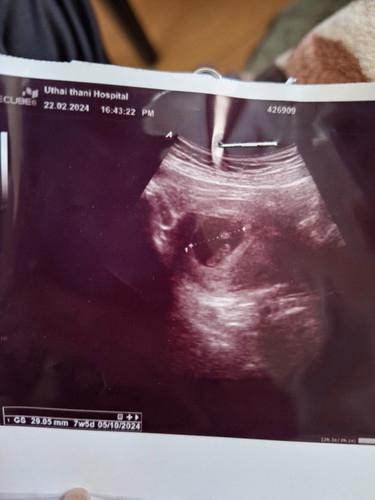

ขนาดที่หมอลากเส้นคือถุงตั้งครรภ์ ส่วนข้างในมีตัวอ่อนและถุงไข่แดงค่ะ ก้อนๆยาวๆนั่นแหละค่ะตัวอ่อน

พบถุงตั้งครรภ์ ขนาด 29.05 มม. อายุรครรภ์ 7วีค5วัน คะเนกำหนดคลอด 5/10/24